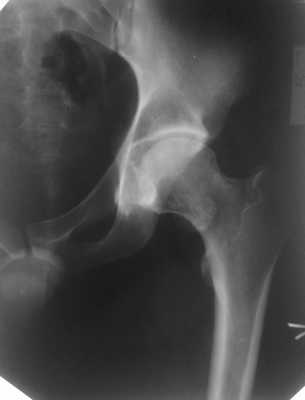

Остеохондрома шейки бедренной кости, хондроматоз тазобедренного сустава

Анамнез: Мужчина, 26 лет. Жалобы на боли.

Описание исследования Дополнительное образование в медиальном отделе шейки бедра. Контуры нижнего отдела вертлужной впадины нечеткие.

Описание исследования В шейке левой бедренной кости определяется образование костной структуры, юкстакортикальное, с переходом кортикального слоя шейки на образование, на широком основании, контуры четкие, структура неоднородная за счет мелких участков хрящевой плотности. Направление роста - от сустава кзади. В полости левого тазобедренного сустава множественные хондроматозные тела на фоне выпота. В передне-нижнем отделе вертлужной впадины полуовальный субхондральный дефект с четким склерозированным контуром, содержимое - хондроматозные тела.